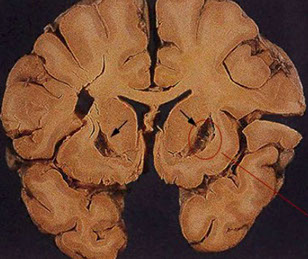

Gross: atrophy of the caudate nucleus and putamen associated with a diffuse neuronal loss.

Huntington disease